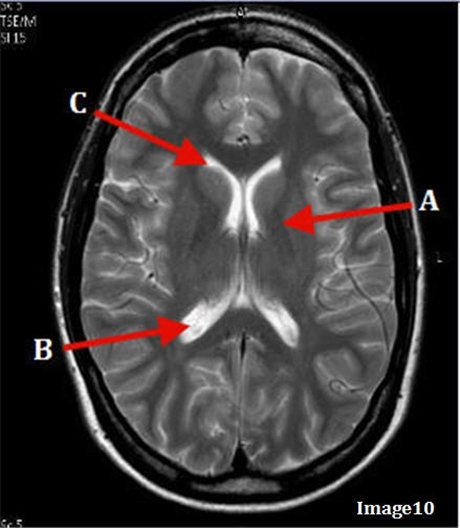

Image weighting and axis

T2 Axial

A

Caudate Nucleus

B

Thalamus

C

Third ventricle

D

Lentiform Nucleus